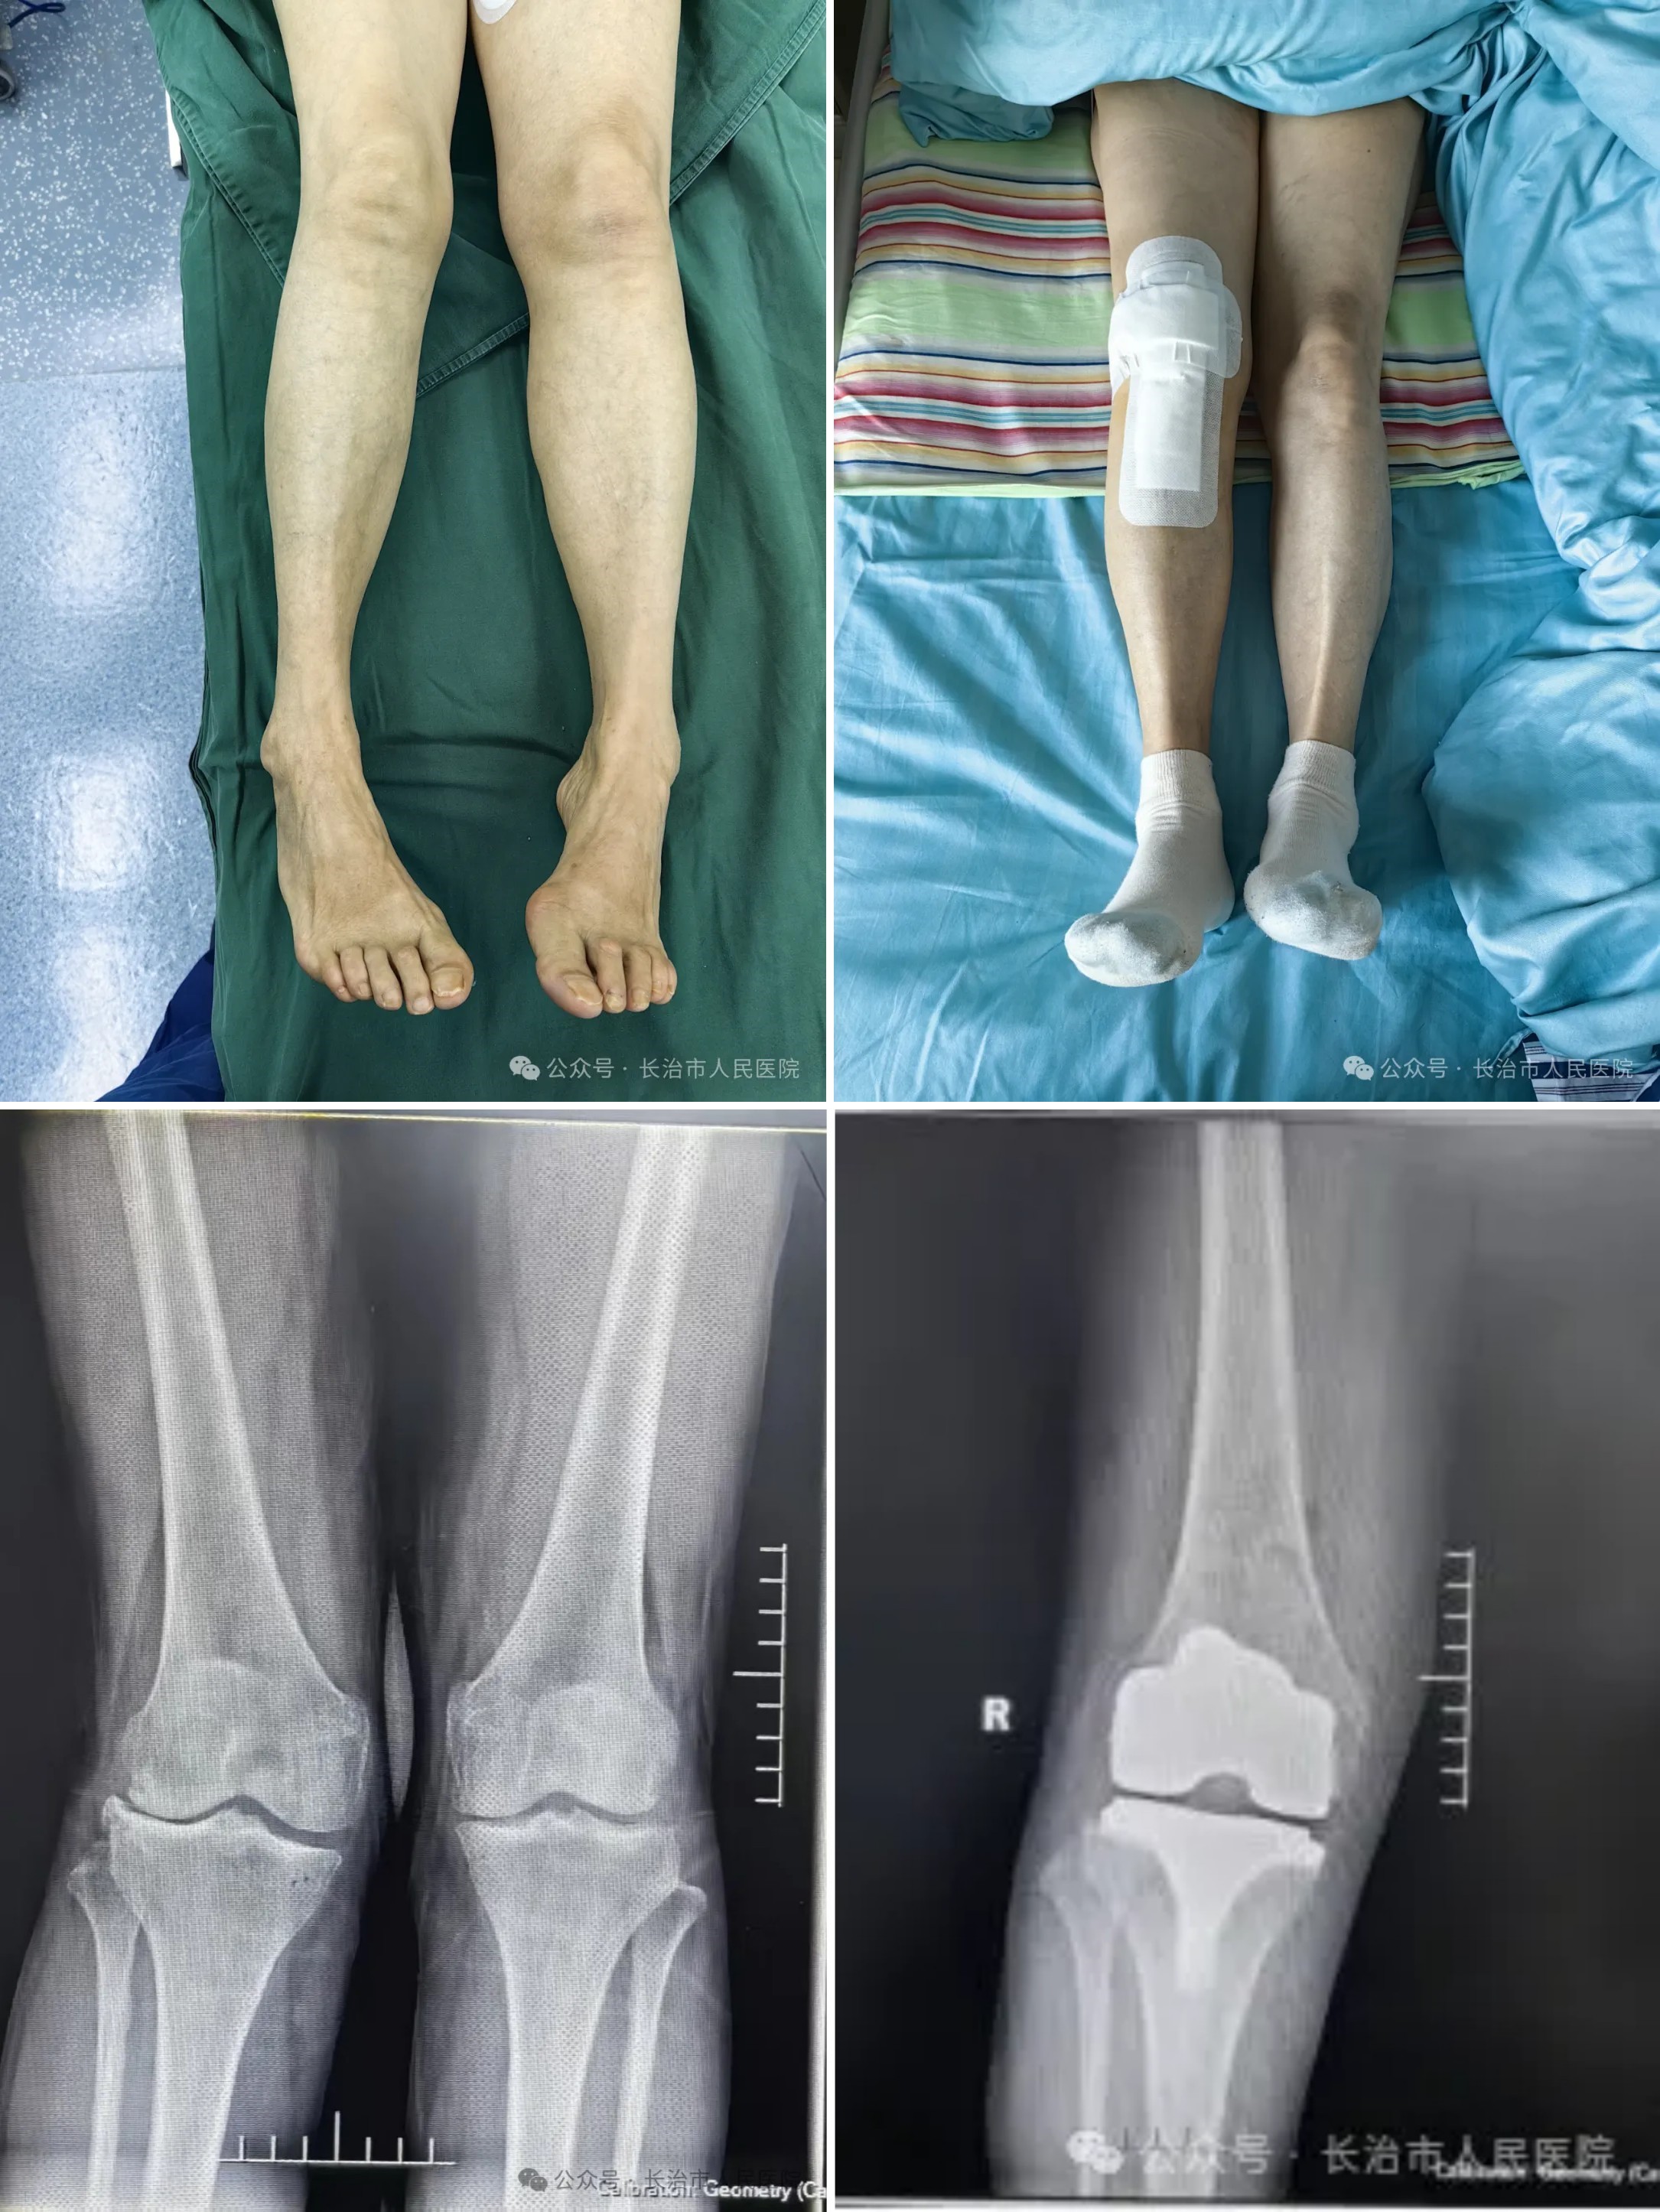

▲患者术前(上左、下左)术后(上右、下右)情况对比

今年70岁的郭阿姨右膝外翻畸形多年,近年来病情持续加重,不仅膝关节疼痛难忍,日常行走、上下楼梯等基本活动也严重受限,腘窝处还逐渐长出囊肿,且增至4cm×1.3cm大小,导致小腿持续性困痛,生活质量大幅下降。到长治市人民医院骨科中心就诊前,郭阿姨尝试过多种保守治疗方法,但症状始终未能改善。

杨森副主任医师团队接诊后,为郭阿姨进行全面检查。影像学结果显示,其右膝外翻畸形严重,关节软骨磨损明显,同时合并腘窝囊肿。团队深入分析后确定,这两种病症实为“同根同源”——膝外翻导致膝关节受力分布异常,长期不均衡负荷加速了软骨磨损,进而使关节液分泌增多,多余的关节液从关节腔薄弱区域突出,最终形成腘窝囊肿。

术后第一天患者即开始康复训练,第二天即可下床活动,一周后膝关节功能明显改善,屈伸活动度恢复至120°,外翻畸形完全矫正,囊肿问题也得到了彻底解决。